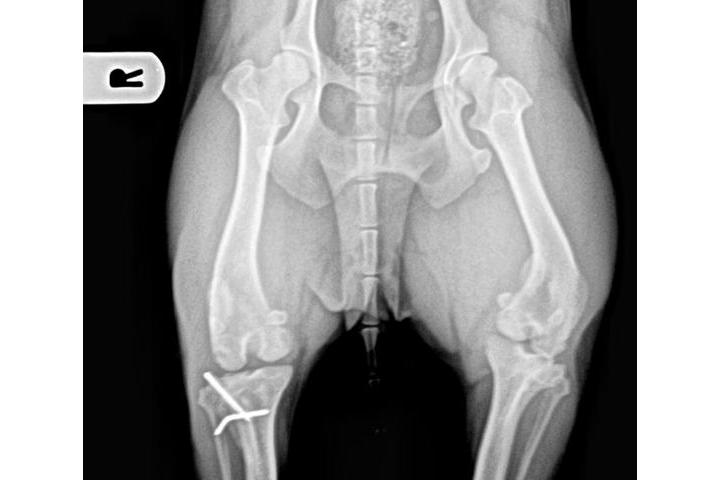

Rx de la rodilla de Snoopy tras la cirugía

Finalmente ya tengo en mi poder el informe quirúrgico y las radiografías del postoperatorio de Snoopy...las voy a publicar enseguida para que veáis la complejidad de la intervención y la sorprendente recuperación de esta maravillosa perrita....el jueves la llevamos a su primera revisión pero os aseguro que es increíble verla saltar y correr con su pAtita nueva....la otra pata ahora se la ve peor y es normal porque se le nota más la curvatura anormal de la luxación....calculamos que a este ritmo de la podrá operar de nuevo antes de lo que pensábamos. Ahora publicaré las radiografías y para el informe necesitaré ayuda porque está en mi mail en un formato raro y necesito a mi hermana y su ordenador....

Comparativa de las patas de Snoopy.